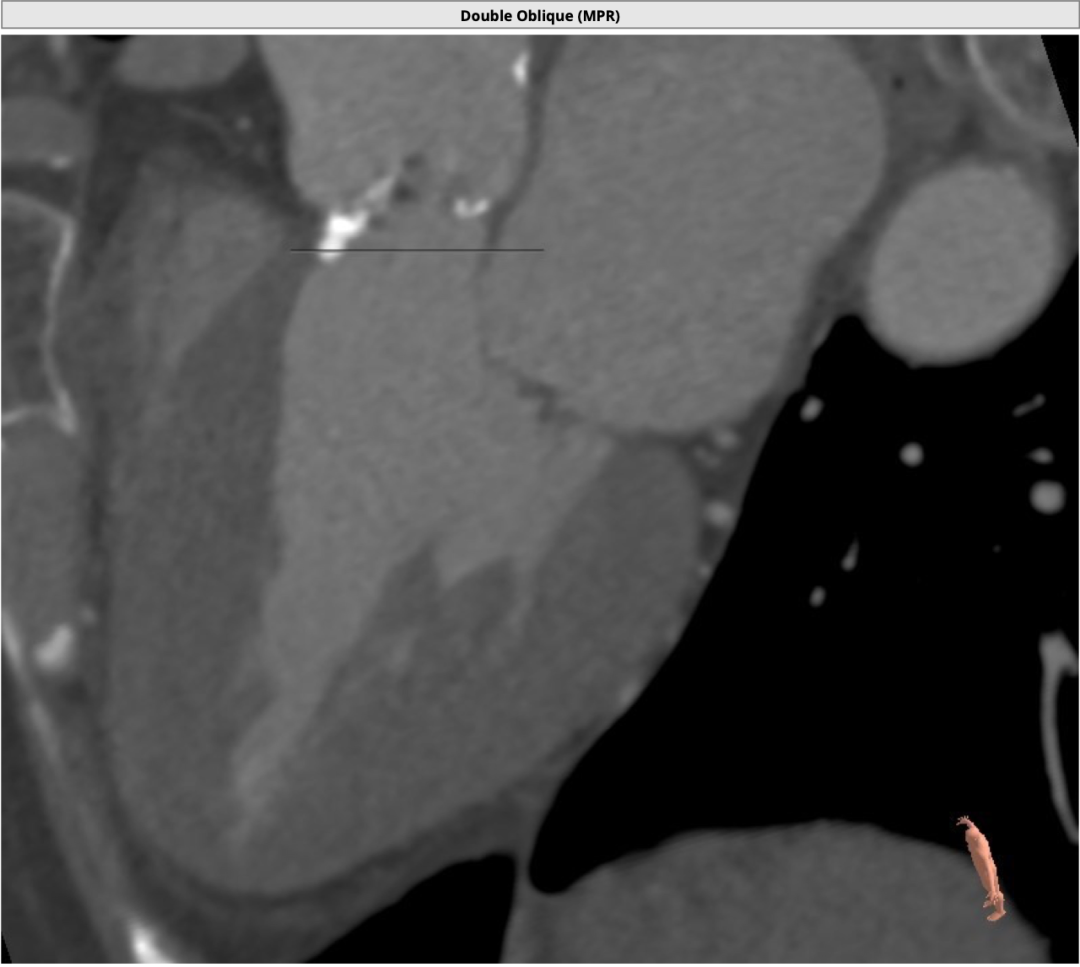

3.png

心室非常肥厚,心腔较小